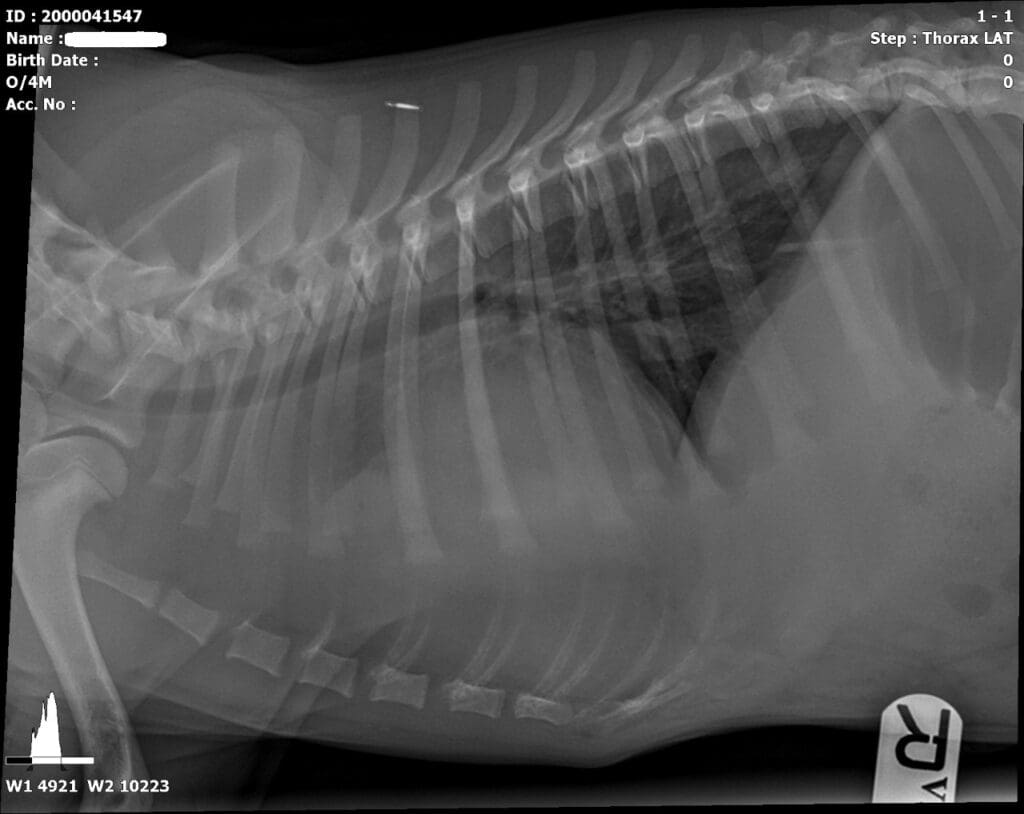

狗狗疝氣案例分享(二)

就診對象:

柯基,5 歲。飼主發現肛門凸出一塊,剃毛後發現肛門旁嚴重腫脹。

就診原因:

肛門周圍出現明顯腫脹並伴隨凸出的異常組織。

臨床檢查:

1. X 光拍攝未見膀胱。

2. 掃描超音波發現膀胱位於屁股後側。

3. 驗血:腎指數偏高。